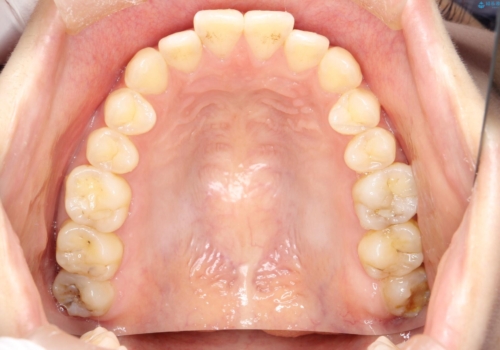

前歯のガタつき、下顎の前突感を治したい インビザライン矯正例

- 治療計画